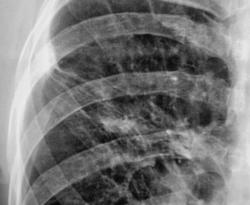

После расшифровку флюорограмм пациента "взяли на контроль". Произведена рентгенография в прямой и правой боковой проекциях.

Всё же я отдал бы предпочтение посттуберкулёзному утолщению плевры, это подкрепляется наличием множества кальцинатов и интесивность тяжестости характерна для фиброза, но ни как для лимфангиита. В большинстве случая имеет место быть выпоту в плевральной полости. Но верификация конечно должна быть на уровне гистологии если есть подозрение.

Пациент, когда-то состоял на учете у фтизиатра, проводилось специфические лечение, хотя - "концов нет". Не нашли ни снимки и карточки. Дело в том, что раньше при ЛПУ было туб. отделение, которое было ликвидировано несколько лет назад, и в процессе ликвидации ликвидировались....

Склоняюсь к посттуберкулезным изменениям. Вероятно очаг был в 3-м сегменте и прилежал к междолевой плевре, отсюда и изменения самой плевры в виде спаек.